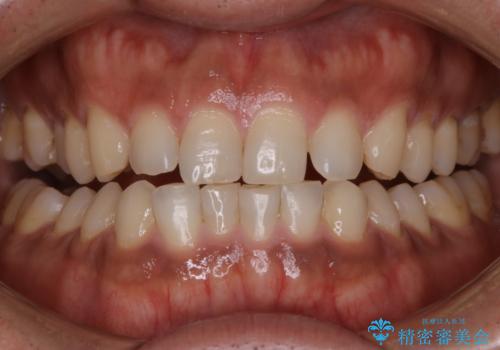

- 20代男性

- 1日

- 1回

- 数年ぶりにホワイトニングを希望とのことで、できる限り白くしたいとのことでした。

オフィスホワイトニングのエクセレントコースを行いました。

- ¥29700費用は治療当時の料金となります